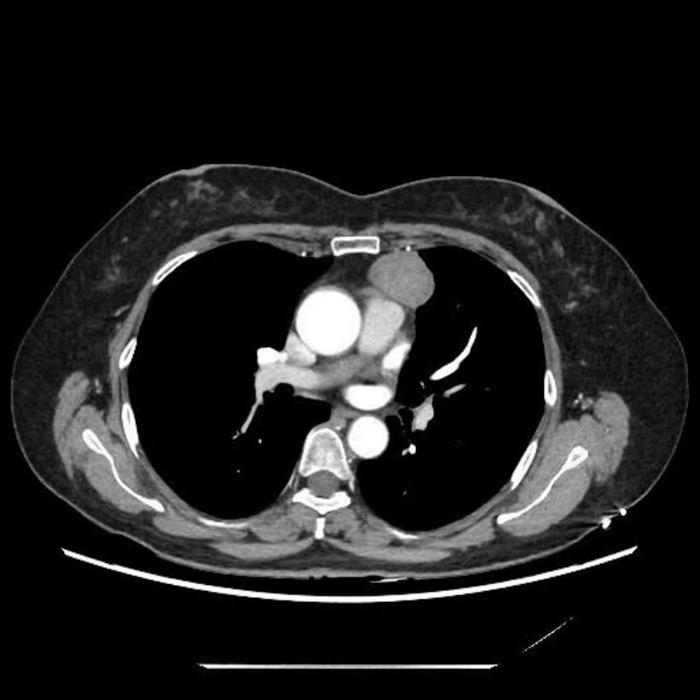

患者为一名43岁女性教师,因体检发现纵隔肿物5个月入院。出于对术后可能影响发声、耽误教学工作的顾虑,患者一度不愿接受手术。传统胸腔镜手术虽属微创,但仍存在器械干扰、视野局限等操作难点。本次采用的“Tubeless麻醉+经皮天平拉钩”技术体系,有效解决了上述问题,实现了更优的手术显露与更小的生理干扰。